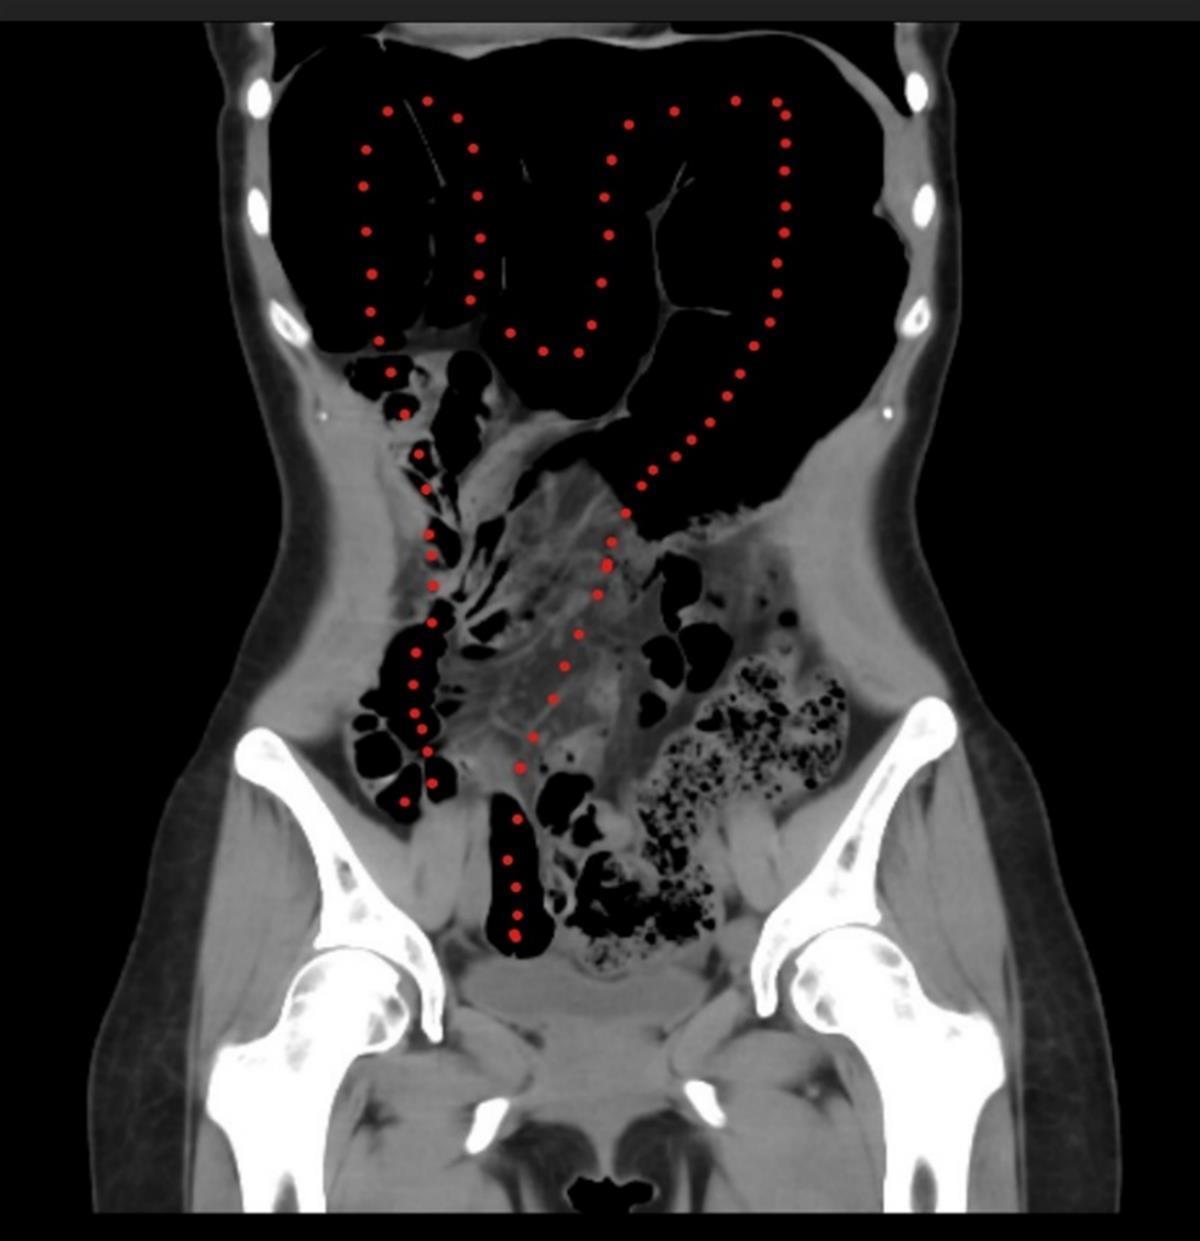

虚线处就是徐女士冗长的乙状结肠

这六年来,徐女士(化姓)总是排便困难、腹胀绞痛,长期只能靠服用泻药来缓解。近两年,徐女士的症状逐渐加重,严重时长达十余天不能排泄,为此她只能减少进食,但腹胀、腹痛越发频繁。四处就医检查,医生发现她的乙状结肠的长度达90厘米,是正常人的2倍多,最终确诊为较为罕见的疾病——乙状结肠冗长症继发巨结肠病。